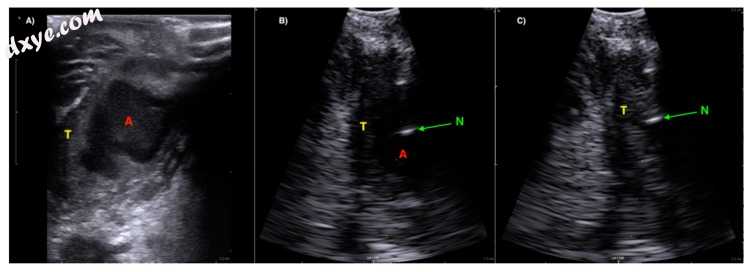

5.jpg

图5

(图像(A))用线性曲棍球棒传感器(BK超声)观察到与帕拉丁扁桃体(T)相关的明确的低回声扁桃体周围脓肿(A)。 (图像(B))使用具有针引导的凸阵钻孔换能器来自同一患者的超声图像。针尖被视为脓肿腔(A)中的低回声反射(N)。 (图像(C))从脓肿腔中成功吸出脓液后的超声图像。